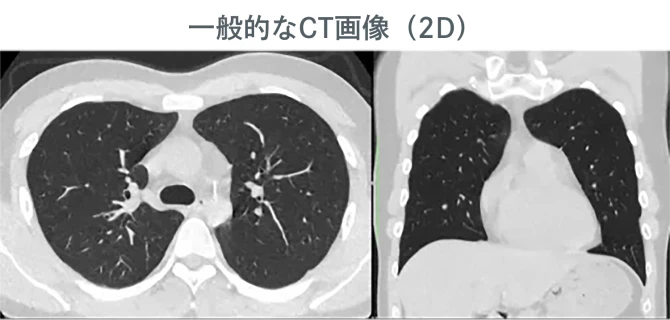

肺+心臓CTとは、胸部全体を撮影し、肺や心臓の状態をすみずみまで詳しく調べる検査です。一般的な健康診断のレントゲンでは見つけにくい病気のサインや、ごく小さな異常を発見することに優れています。

一般的な人間ドックでは胸部X線(レントゲン)での検査のみとなるため、胸部の健康を維持するためには別途CT検査を受診いただくことを推奨しています。

当院の画像は高画質なだけでなく、リアル3D画像も作成し、お渡しします。

病変の大きさ、形状、周囲組織との位置関係などを立体的に評価できるため、診断の正確性が向上します。また、異変が視覚的にわかりやすいため、受診者様も理解が容易になります。